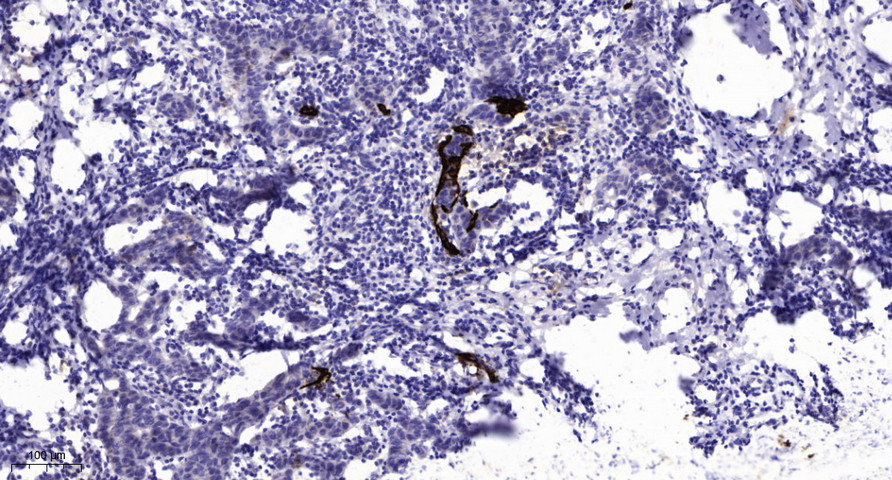

Main InformationTargetMFRPHost SpeciesRabbitReactivityHuman, MouseApplicationsIHC, IF, WBMW62kD (Observed)Conjugate/ModificationUnmodifiedDetailed InformationRecommended Dilution RatioIHC 1:50-200; WB 1:500-2000; IF 1:50-200FormulationLiquid in PBS containing 50% glycerol, 0.5% BSA and 0.02% sodium azide.SpecificityThis antibody detects endogenous levels of human MFRPPurificationThe antibody was affinity-purified from rabbit antiserum by affinity-chromatography using epitope-specific immunogen.Storage-15°C to -25°C/1 year(Do not lower than -25°C)Concentration1 mg/mlMW(Observed)62kDModificationUnmodifiedClonalityPolyclonalIsotypeIgGAntigen&Target InformationImmunogen:Synthesized peptide derived from human MFRPSpecificity:This antibody detects endogenous levels of human MFRPGene Name:MFRPProtein Name:MFRPOther Name:Membrane frizzled-related protein ; Membrane-type frizzled-related protein ;Background:membrane frizzled-related protein(MFRP) Homo sapiens This gene encodes a member of the frizzled-related protein family. The encoded protein plays an important role in eye development and mutations in this gene have been associated with nanophthalmos, posterior microphthalmia, retinitis pigmentosa, foveoschisis, and optic disc drusen. The protein is encoded by a bicistronic transcript which also encodes C1q and tumor necrosis factor related protein 5 (C1QTNF5). [provided by RefSeq, Jun 2013],Function:developmental stage:Expressed in fetal brain.,Disease:Defects in C1QTNF5 are a cause of late-onset retinal degeneration (LORD) [MIM:605670]. LORD is an autosomal dominant disorder characterized by onset in the fifth to sixth decade with night blindness and punctate yellow-white deposits in the retinal fundus, progressing to severe central and peripheral degeneration, with choroidal neovascularization and chorioretinal atrophy.,Disease:Defects in MFRP are the cause of microphthalmia MFRP-related (MCOPMFRP) [MIM:611040]. Microphthalmia is a clinically heterogeneous disorder of eye formation, ranging from small size of a single eye to complete bilateral absence of ocular tissues. Ocular abnormalities like opacities of the cornea and lens, scaring of the retina and choroid, cataract and other abnormalities like cataract may also be present. MCOPMFRP is characterized by posterior microphthalmia, retinitis pigmentosa, foveoschisis and optic disc drusen.,Disease:Defects in MFRP are the cause of nanophthalmos 2 (NNO2) [MIM:609549]. NNO2 is a rare autosomal recessive disorder of eye development characterized by extreme hyperopia and small functional eyes.,Function:May play a role in eye development.,similarity:Contains 1 C1q domain.,similarity:Contains 1 collagen-like domain.,similarity:Contains 1 FZ (frizzled) domain.,similarity:Contains 2 CUB domains.,similarity:Contains 2 LDL-receptor class A domains.,tissue specificity:Specifically expressed in brain. Strongly expressed in medulla oblongata and to a lower extent in hippocampus and corpus callosum. Expressed in keratinocytes.,Cellular Localization:Apical cell membrane ; Single-pass type II membrane protein .Tissue Expression:Specifically expressed in brain. Strongly expressed in medulla oblongata and to a lower extent in hippocampus and corpus callosum. Expressed in keratinocytes.